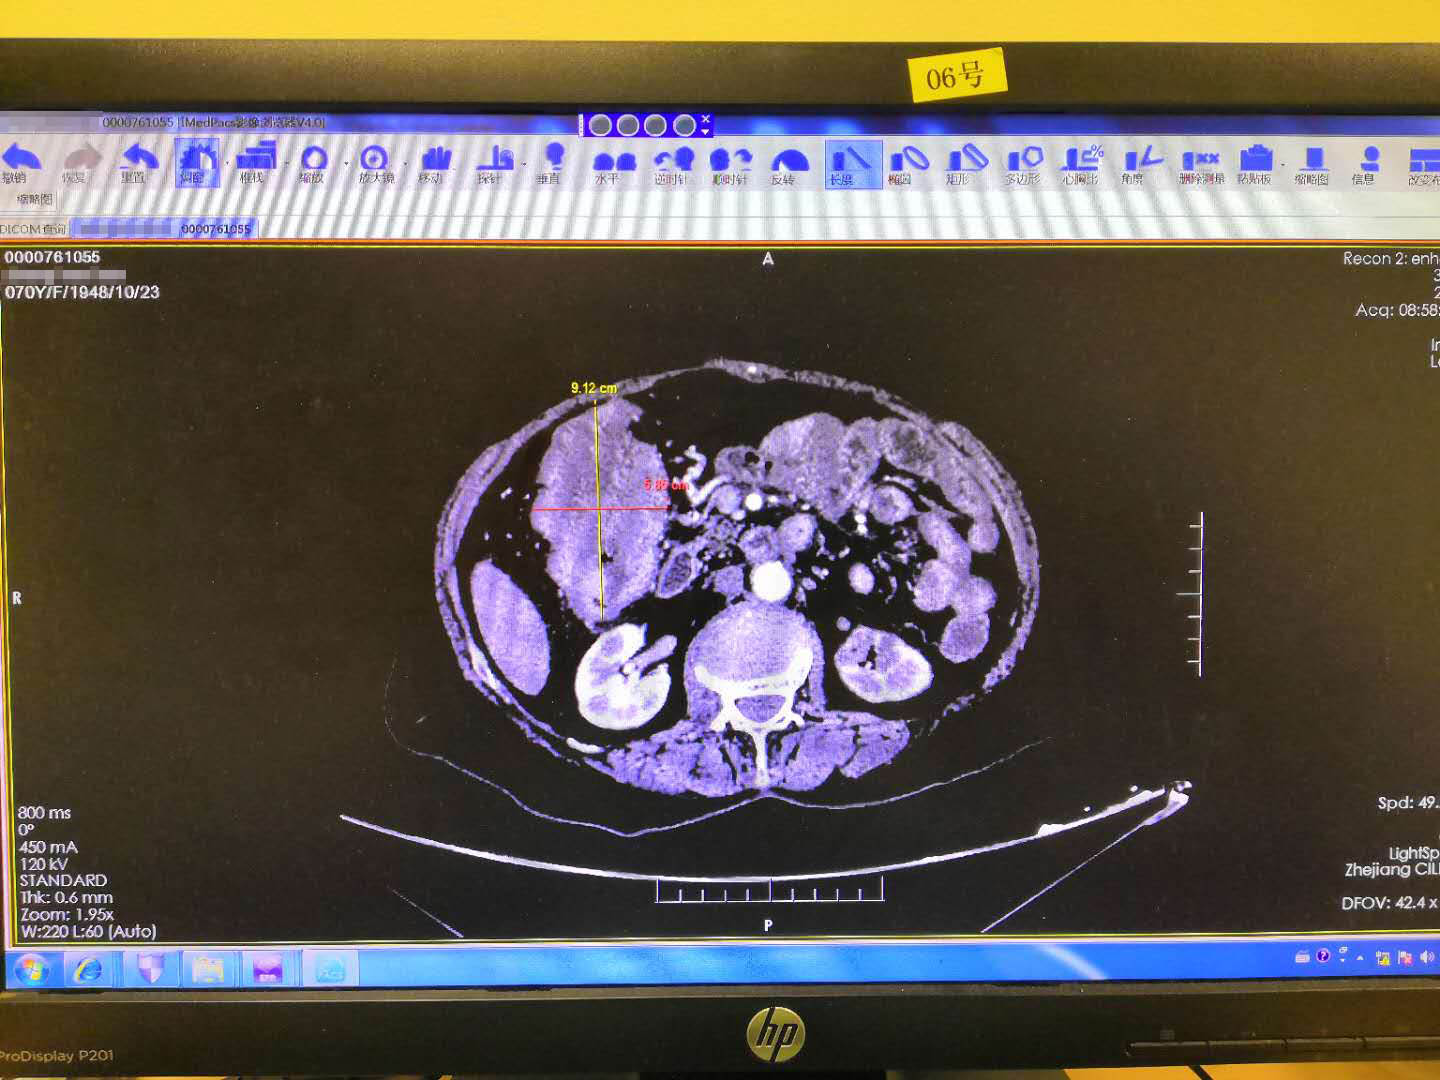

元旦这天,在孩子的陪同下我再次来到了慈林医院,求诊于消化内科。消化内科的医生听了我的描述也怀疑是肿瘤的复发,在随后的增强CT中发现了我的结肠肝曲域有一个4X8X6的巨大肿瘤。